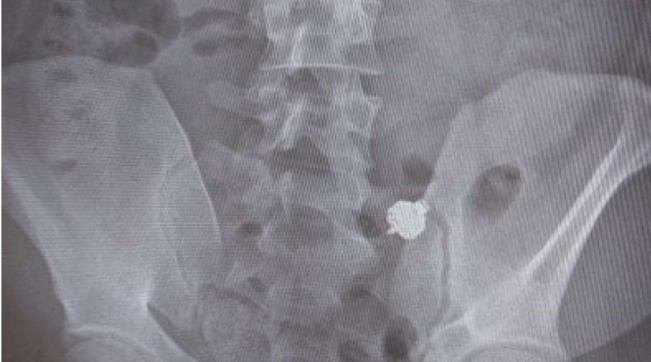

A Bolzano un uomo è stato scoperto mentre tentava di imbrogliare all’esame teorico per la patente, utilizzando un micro-auricolare per farsi suggerire le risposte esatte. Resosi conto di essere stato “pizzicato” dagli agenti di polizia in borghese presenti in aula, il candidato si è sfilato l’auricolare dall’orecchio e l’ha ingoiato. A quel punto è scattata la denuncia per i reati di presentazione di esami opera di altri (una legge del 1925 ancora in vigore) e per falsità ideologica per induzione. Ora rischia la pena della reclusione da sei mesi a due anni.